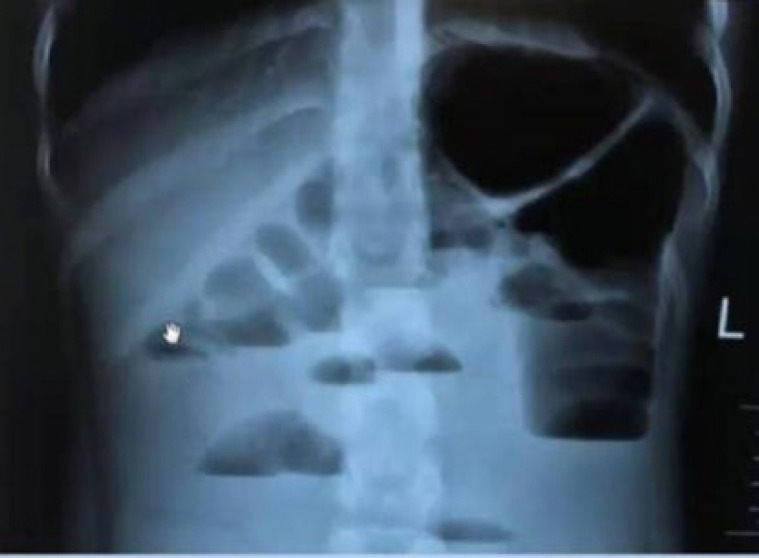

The occurrence of rectosigmoid junction inflammatory myofibroblastic tumor (IMT) is uncommon in children. This is a rare form of mesenchymal tumor, belonging to the category of soft tissue tumors, and can be found at any anatomical site from the central nervous system to the gastrointestinal tract. Our patient was a 10-year-old male subject complaining of lack of defecation and constipation. The patient had decreased the frequency of defecation and constipation about two weeks before his referral and had not improved despite the use of laxatives. The abdomen was completely distended and there was no tenderness or guarding in the examination. Several airfluid levels are shown on the abdominal X-ray. In the ultrasound, free fluid was reported in the interlobular and pelvic spaces. The patient was transferred into the operating room. A tumor of the rectosigmoid junction was detected. Histopathologic studies showed evidence of IMT. IMT is a rare neoplasm of unknown origin, which may occur in various sites of the body. Complete surgical removal is usually curative, but early detection of recurrence is required. Treatment options include chemotherapy, radiation therapy, and immunotherapy. Further investigations are needed to improve the understanding and management of this rare tumor.